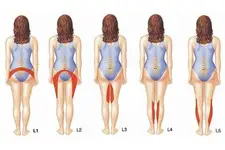

Bel Fıtığı ve Platin Takılması: Genel BilgilerBel fıtığı, omurganın aşağı kısmında yer alan disklerin (intervertebral disklerin) yıpranması sonucunda oluşan bir rahatsızlıktır. Bu durum, diskin içindeki jel benzeri maddelerin dışarı çıkması ve sinirlere baskı yapmasıyla karakterizedir. Bel fıtığı, sırt ağrısı, bacaklarda uyuşma, güçsüzlük ve hareket kısıtlılığı gibi belirtilerle kendini gösterir. Platin Takılması: Neden ve Nasıl Uygulanır? Bel fıtığı tedavisinde, cerrahi müdahaleler gerekebilir. Bu tür durumlarda, omurga stabilitesini sağlamak amacıyla platin (metal veya biyomateryal) takılması tercih edilebilir. Platin, omurga yapılarını bir arada tutarak iyileşme sürecine destek olur. Platin Takılmasının Zararları Platin takılmasının bazı potansiyel zararları ve komplikasyonları şunlardır:

Alternatif Tedavi Yöntemleri Bel fıtığı için platin takılması dışında birçok alternatif tedavi yöntemi bulunmaktadır:

Sonuç Bel fıtığı cerrahisi, platin takılması gibi yöntemlerle tedavi edilebilirken, bu süreçte dikkat edilmesi gereken birçok risk ve komplikasyon bulunmaktadır. Bel fıtığı tedavisinde bireysel ihtiyaçlara uygun en etkili yöntemin belirlenmesi, hastanın genel sağlığı ve yaşam kalitesi açısından büyük önem taşımaktadır. Dolayısıyla, hastaların tedavi sürecinde uzman hekimlerin görüşlerine başvurmaları ve alternatif tedavi yöntemlerini araştırmaları önerilmektedir. Ekstra Bilgiler Bel fıtığı tedavisinde platin takılmasının yanı sıra, bireylerin yaşam tarzlarını değiştirmeleri, düzenli egzersiz yapmaları ve kilo kontrolü sağlamaları da önemlidir. Ayrıca, bel fıtığı riski taşıyan meslek grupları için ergonomik çalışma ortamlarının sağlanması önerilmektedir. |